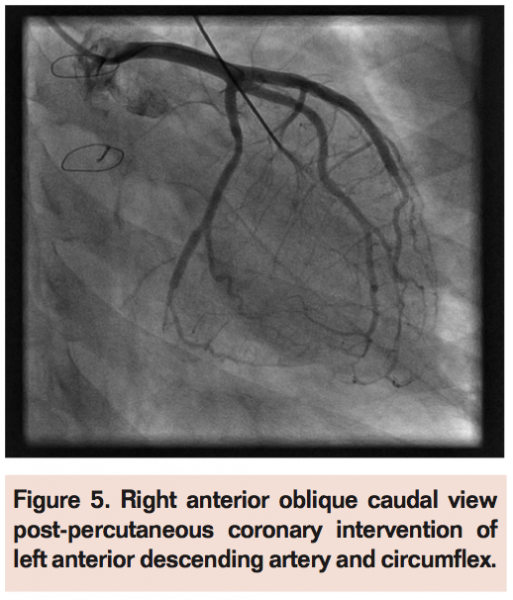

Prior to the sterile prep, the pelvis was wrapped in a lead apron and deep conscious sedation was obtained with propofol administered by cardiac anesthesiology. We obtained arterial access with a micro-puncture system and the patient was given 2.5 mg of intra-arterial verapamil via a 4 Fr x 5 cm dilator. She was systemically anticoagulated with heparin. We attempted to use a sheathless system by advancing a 5 Fr EBU 3.0 mm guide catheter utilizing a 4 Fr x 125 cm MP diagnostic catheter as an introducer. The whole system was advanced over a 0.035-inch guide wire that had been previously advanced to the ascending aorta. However, there was significant resistance in advancing the catheter through the proximal radial artery. Ultimately a 5 Fr x 11 cm hydrophilic sheath was inserted into the left radial artery. The guide catheter could then easily advance into the ascending aorta, allowing for intubation of the left main coronary artery. The LAD was wired with a 0.014-inch x 180 cm middleweight coronary guidewire. The lesion was pre-dilated with a 2.0 mm compliant balloon and ultimately treated with a 2.5 mm Cypher drug-eluting stent. The stent was post-dilated with a 2.5 mm non-compliant balloon resulting in an excellent angiographic result. Next, the circumflex artery was wired and directly stented with a 2.25 mm Cypher drug-eluting stent. Cineangiography confirmed an excellent result (Figures 4 and 5). The sheath was removed and the access site was compressed with a radial compression device with care given to ensuring patent hemostasis. A total radiation dose of 358 mGy was required for the procedure. On the following day, however, she had tenderness over the left radial artery access site and a pulse was difficult to palpate. The reverse Allen’s test at the bedside suggested that the radial artery might have occluded. However, at 1-week follow-up, her pain had significantly improved and a reverse Allen’s test showed patency of the radial artery. Pseudoaneurysm was not present based on physical examination.